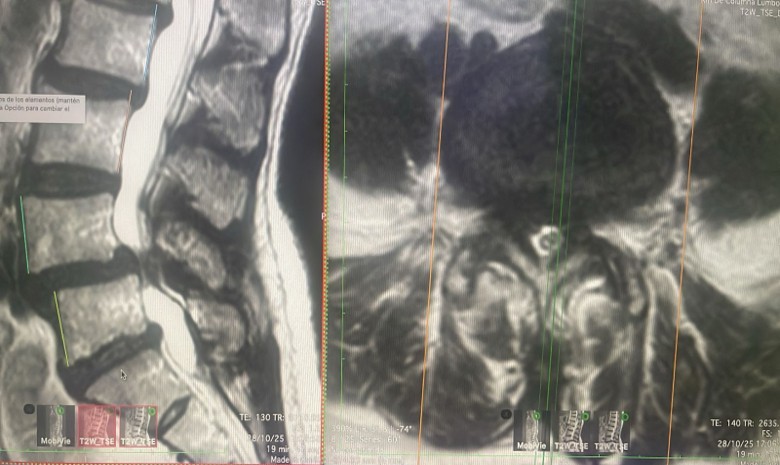

¿Cómo diagnosticarla? A través de exámenes de imagen como Resonancia Magnética Nuclear (RMN) es la más utilizada y efectiva para el diagnóstico de la hernia de disco cervical, ofrece imágenes de alta resolución de las partes blandas (disco, hernia, nervios). La Tomografía Computarizada (TC) también puede ser útil para evaluar la parte ósea. Los estudios radiográficos de proyección dinámica son importantes para valorar la estabilidad del segmento afectado (espondilolistesis).

Diagnóstico: La Resonancia Magnética (RM) es de elección para el diagnóstico de la hernia de disco lumbar, se identifica la hernia, características y nivel de compresión de la raíz nerviosa. La Tomografía Computarizada (TC) también puede ser útil, aunque su imagen no es tan nítida para las partes blandas.

Diagnóstico: Además de la sintomatología compatible, se requieren pruebas de imagen:

• Radiografía lumbar (AP, lateral y funcional): Ayuda a determinar anomalías óseas, tipo de curvatura e inestabilidad de la columna.

• RM lumbar: Es la prueba de elección, ya que proporciona información detallada sobre estructuras óseas (aunque menos definida que la TC) y partes blandas como el ligamento amarillo, discos intervertebrales y quistes sinoviales.

• TC lumbar: Ofrece una buena resolución de las estructuras óseas.